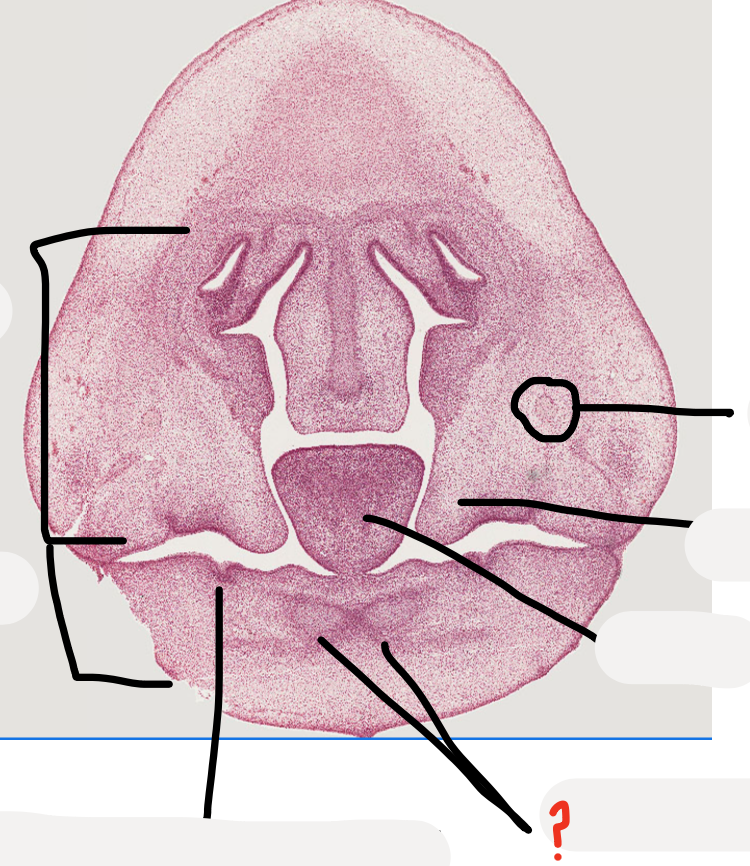

Not at all

what age is this specimen? why?

A

Week 8, palatal shelves elevated but not fused yet

which forms first maxilla or mandible?

palatal shelves

tooth germ

meckel's cartilage

developing mandible

inferior alveolar nerve